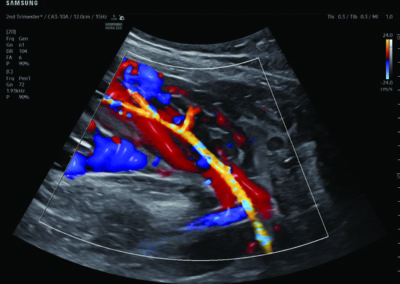

Procedural Services

Comprehensive, advanced and expert MFM care for high-risk pregnancies